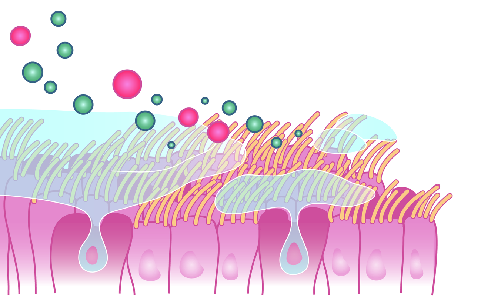

Detailreiche Fotografien aus der medizinischen Praxis ergänzen die Texte; moderne, genaue,

wissenschaftliche Zeichnungen geben Einblick in die Anatomie und die Funktion der Lunge und

anderer Organe.